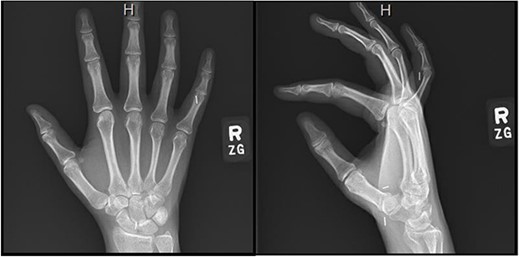

Right hand imaging 1-month status post revision CTR demonstrating hemoclip placement with initial asymptomatic migration of a single clip to the small finger proximal interphalangeal joint.